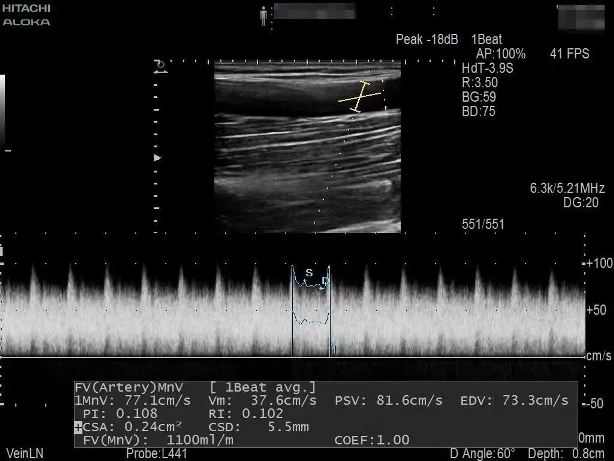

患者1年前出現(xiàn)周身乏力伴有雙下肢水腫癥狀,在外院行“為腎透析的動(dòng)靜脈造瘺術(shù)”后規(guī)律透析治療。因內(nèi)瘺無震顫2日,為求系統(tǒng)治療來院,入院后腎內(nèi)科金明花主任帶領(lǐng)醫(yī)護(hù)團(tuán)隊(duì)立即完善相關(guān)檢查,診斷為:動(dòng)靜脈內(nèi)瘺血栓形成,經(jīng)超聲檢查發(fā)現(xiàn)動(dòng)靜脈內(nèi)瘺血栓形成狹窄,最窄處內(nèi)徑約1.6mm。

為了節(jié)約患者有限的血管資源,盡早治療,經(jīng)過腎病內(nèi)科金明花主任及科室共同討論并爭(zhēng)得患者家屬同意后,決定對(duì)患者進(jìn)行超聲引導(dǎo)下動(dòng)靜脈內(nèi)瘺球囊擴(kuò)張術(shù)+血栓碎栓術(shù)解決內(nèi)瘺狹窄及血栓。手術(shù)過程中金明花主任在內(nèi)瘺狹窄位置近心端進(jìn)行穿刺,沿穿刺針置入導(dǎo)絲、置入血管鞘,在超聲實(shí)時(shí)引導(dǎo)下球囊到達(dá)病變部位,緩慢擴(kuò)張球囊,解決狹窄病變,并壓碎血栓,使內(nèi)瘺通暢。整個(gè)手術(shù)僅用30分鐘,用時(shí)少,效果明顯,術(shù)后內(nèi)瘺血管雜音及震顫明顯,手術(shù)效果立竿見影。